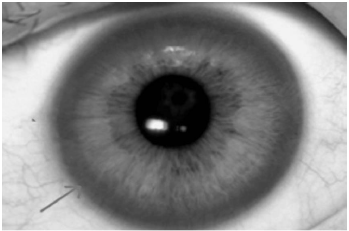

Ao exame: Lúcida, orientada, porém com disartria e disfonia, eupneica em ar ambiente, anictérica, afebril. FC: 64 bpm, PA: 110x60 mmHg, SatO2: 97%. Presença de marcha atáxica, tremor de repouso, dismetria, e um halo marrom-dourado na periferia da córnea e contornando a íris (figura abaixo – seta) em ambos os olhos. MVUA sem ruídos adventícios, ritmo cardíaco regular em 2T sem sopros ou turgência jugular. Fígado palpável a 8 cm do rebordo costal (hepatimetria 14 cm). MMII sem edema.